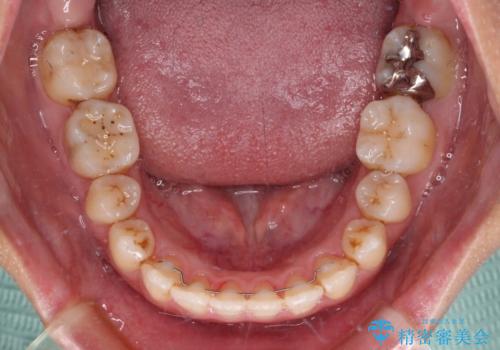

上顎の拡大に伴い反対咬合があっという間に改善されました。

元々の歯列不整は軽微であったため、僅か1年の期間で治療を終えることができました。